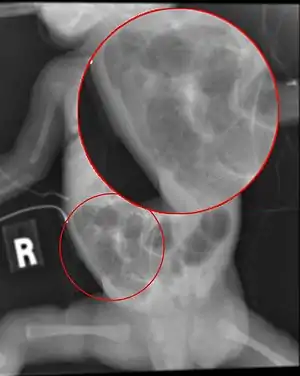

| Radiograph of a baby with necrotizing enterocolitis | |

The diagnosis is usually suspected clinically but often requires the aid of diagnostic imaging modalities, most commonly radiography. Specific radiographic signs of NEC are associated with specific Bell's stages of the disease:[13]

- Specific radiologic signs (pneumatosis intestinalis or portal venous gas

- Severe radiologic signs (pneumoperitoneum)

Ultrasonography has proven to be useful as it may detect signs and complications of NEC before they are evident on radiographs, specifically in cases that involve a paucity of bowel gas, a gasless abdomen, or a sentinel loop.[15] Diagnosis is ultimately made in 5–10% of very-low-birth-weight infants (<1,500g).[16]